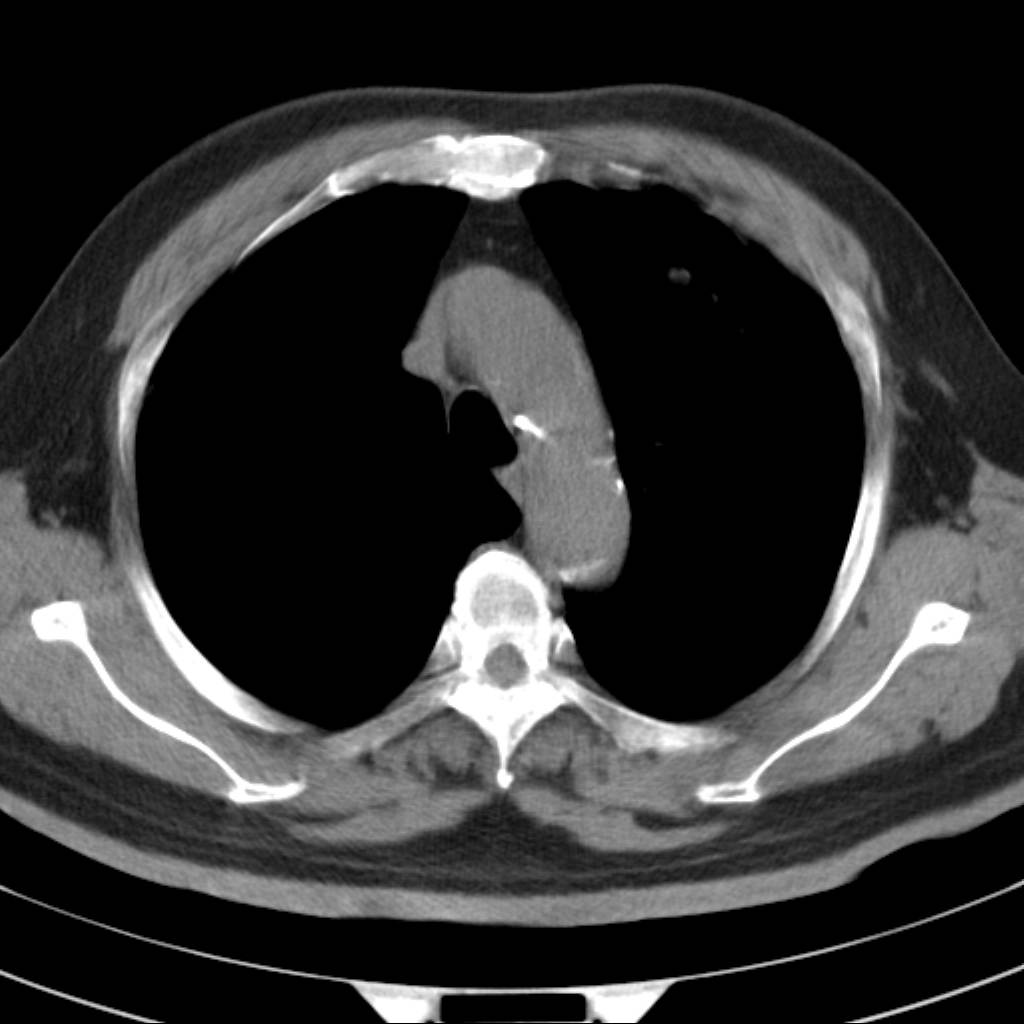

标题: CT18644:男,82岁,体检发现左肺阴影. [打印本页]

标题: CT18644:男,82岁,体检发现左肺阴影.

岁数太大,没有增强。麻烦见过的,给个诊断,顺便再说说病因

左侧中心型肺癌并粘液栓形成。很典型的。手套征。

支持 左肺上叶中央型肺癌并支气管内粘液栓形成。

考虑左肺上叶中央型肺癌并支气管内粘液栓形成。

支持 左肺上叶中央型肺癌并支气管内粘液栓形成,阻塞性肺炎

考虎左肺上叶中央型肺癌并支气管内黏液栓形成,不能增强是个遗憾,期待复查结果。

左肺上叶中央型肺癌